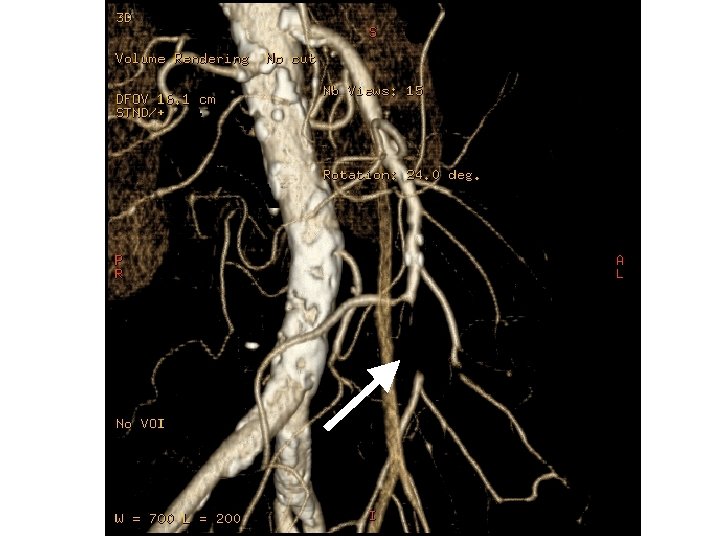

ANGIO-TC • Importante ateromatosis, ya conocida. • Demuestra la oclusión del tercio medio de la arteria mesentérica superior. • Revascularización a expensas de colaterales. • Permite establecer, por fin, el diagnóstico de isquemia.